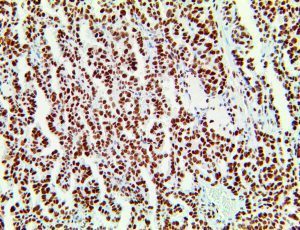

It is the ICU physician who is most likely to witness one of the deadliest manifestations of the abnormal immunological response, the cytokine storm syndrome (CSS). This response is also referred to by some as the cytokine release syndrome (CRS). CSS is characterized by continuous activation and expansion of macrophage and lymphocyte populations, which secrete large amounts of cytokines, causing the cytokine storm. This massive cytokine release is akin to hemophagocytic lymphohistiocytosis (HLH) disease, a syndrome characterized by initial unchecked and persistent activation of cytotoxic T lymphocytes and NK cells.

Clinical and laboratory manifestations of HLH include fever, enlarged liver and/or spleen, neurologic dysfunction, coagulopathy, liver dysfunction, cytopenias (i.e., low levels of erythrocytes, leukocytes, and/or platelets), hypertriglyceridemia, hyperferritinemia, hemophagocytosis, and eventually diminished NK cell activity as the immune system becomes progressively paralyzed. HLH can be familial (primary HLH) or secondary to another disease process (sHLH), such as rheumatic disease, in which it is referred to as macrophage activation syndrome (MAS, characterized by elevated ferritin).